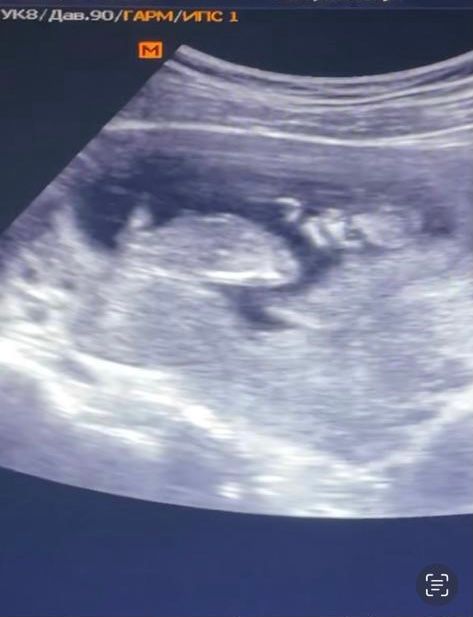

пол на узи , 14 недель Узи пол ребёнка